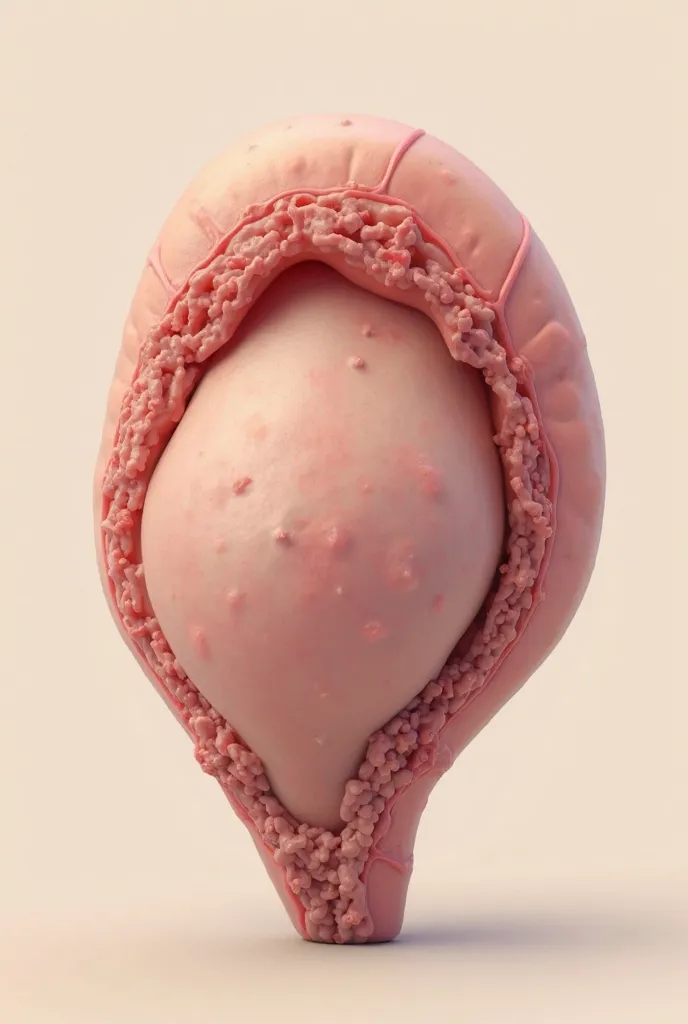

Image of a 10-week-old embryo in a uterus, captura, maternal photography 4 k

Image of a 10-week-old embryo in a uterus, captura, maternal photography 4 k, high quality scan, extremely high quality scan, high resolution scan,, video still, feto, webcam footage, high resolution scan, Escaneo profesional de alta calidad, metraje realista. hiper realista

Image of a 10-week-old embryo in a uterus